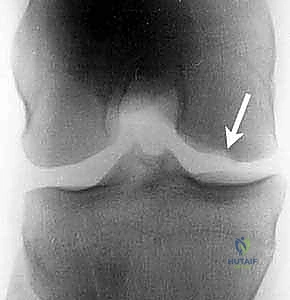

- الأشعة السينية (X-Rays): تُعد الخطوة الأولى لاستبعاد الكسور وتقييم الهيكل العظمي العام، وغالباً ما تُظهر الآفة في المراحل المتقدمة.